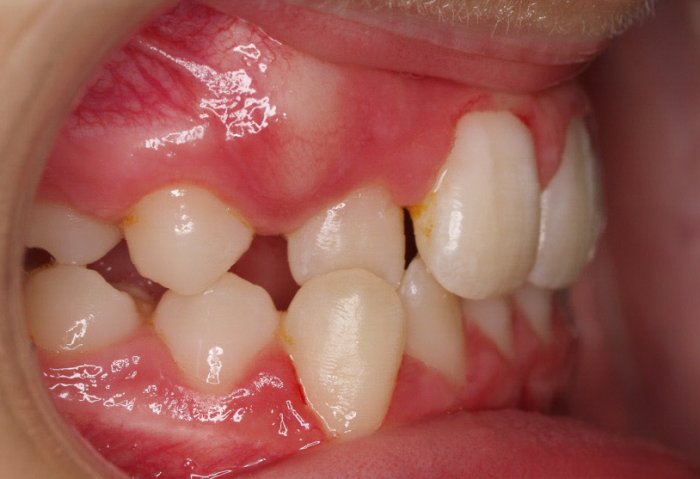

El paciente A.J. de 11 años, acude a nuestra consulta con apiñamiento maxilar importante. El canino lateral (12) está en mordida cruzada. Presenta una Clase II molar y canina, y la línea media está desviada. Se realizó un tratamiento con brackets autoligables metálicos de smartclip 022. La duración del tratamiento fue de 22 meses.